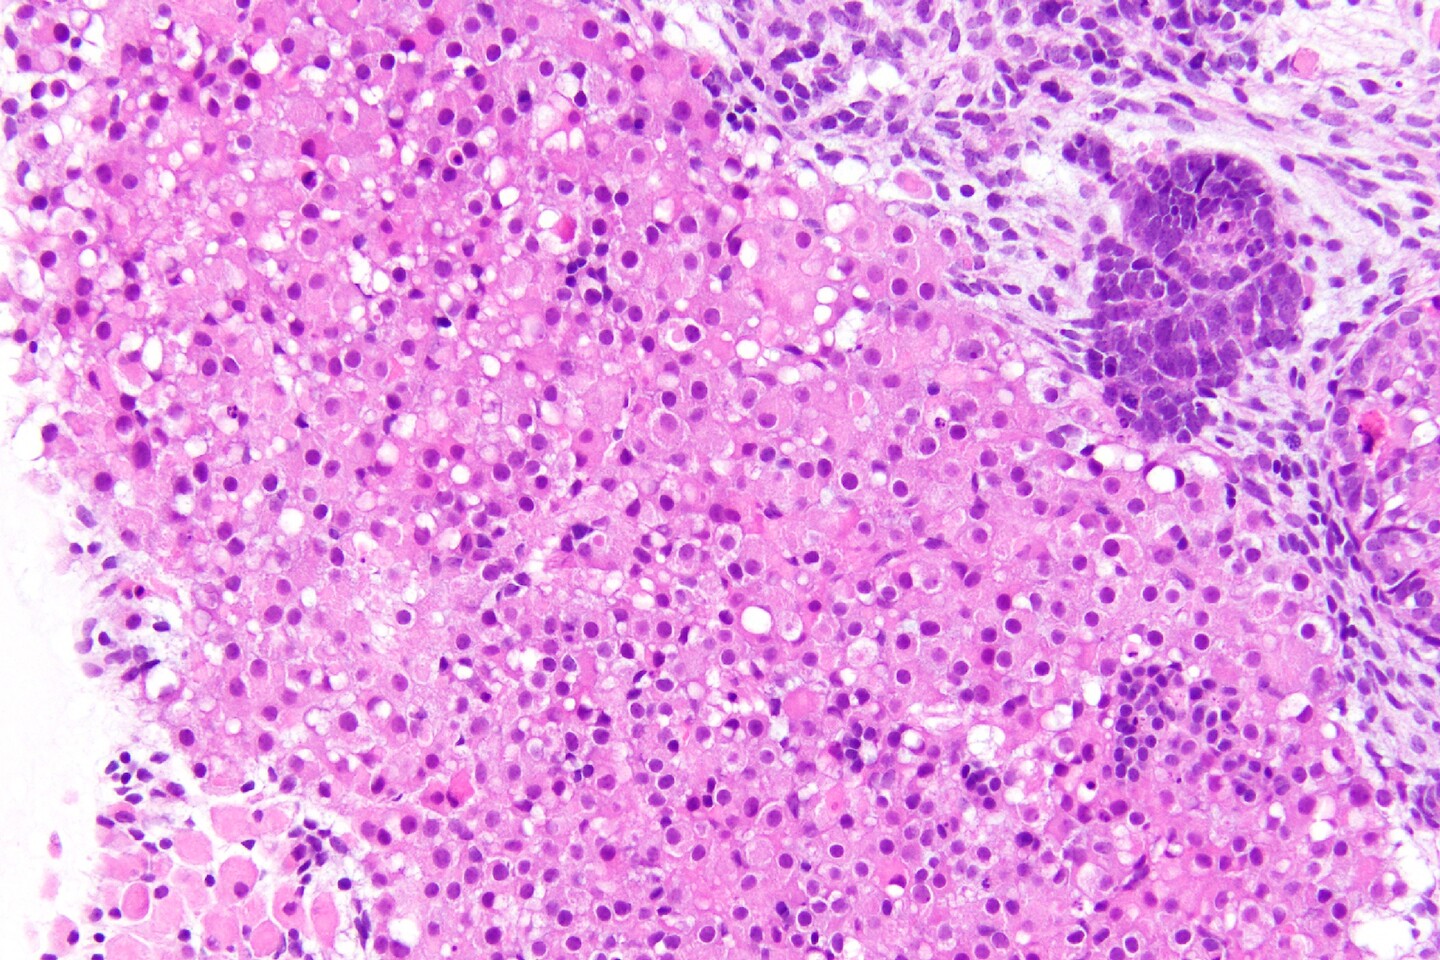

“The process we developed was highly efficient, with around 50% of cells in organoids acquiring adrenocortical cell fate,” says Michinori Mayama, a postdoc in Sasaki’s lab and a lead author on the study. “The ovoid cells with voluminous pink cytoplasm and relatively small nuclei that we saw in our cultures are very characteristic of human adrenal cells at that stage.”